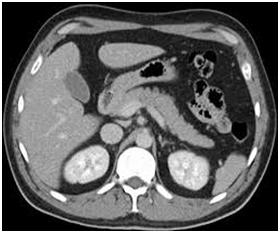

Your doctor has ordered a CT (Computed Tomography) of your abdomen. CT is an advanced form of X-rays that uses a narrow X-ray beam and advanced computer software to create detailed cross-sectional images of the body organs.